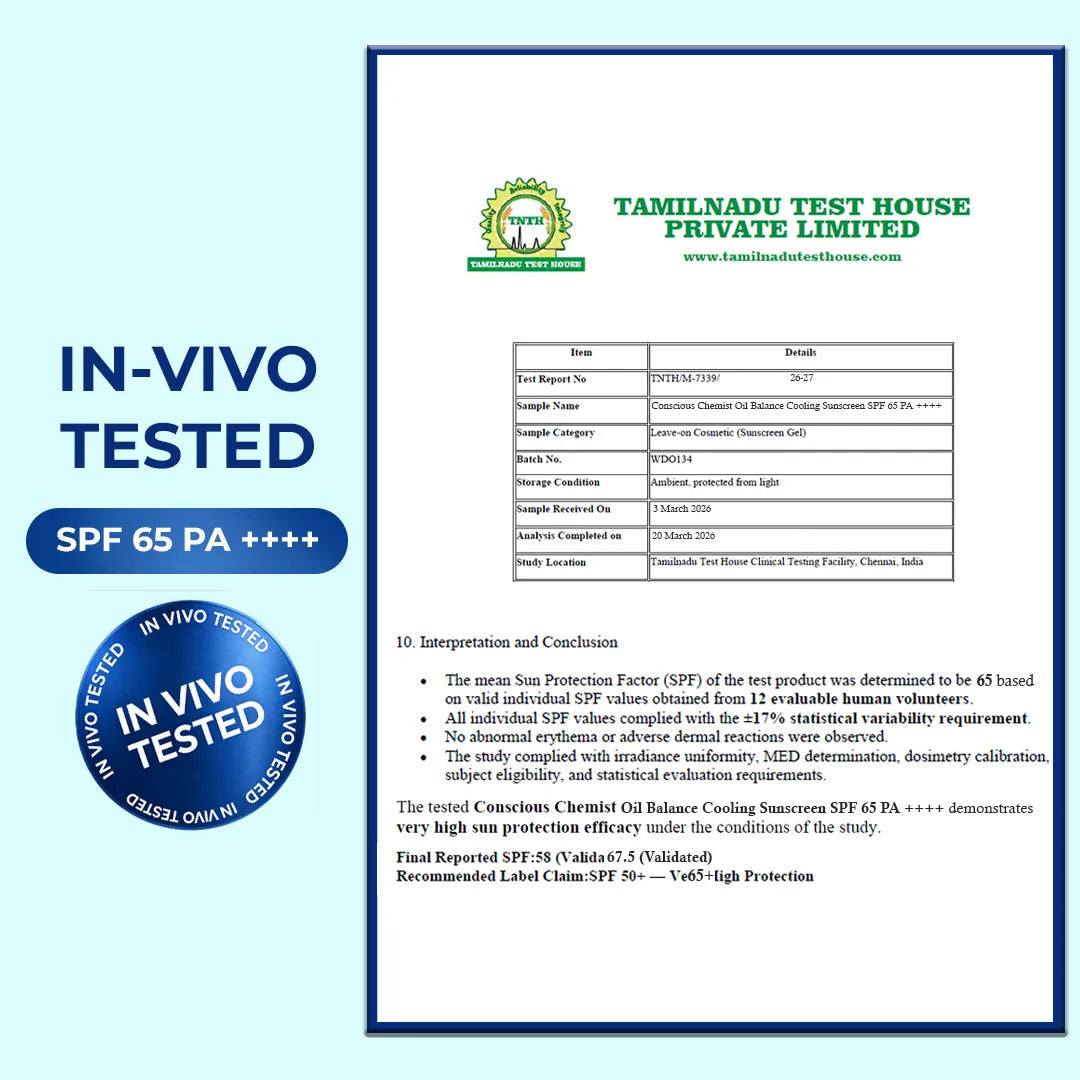

Cooling Fluid Sunscreen | SPF 65 PA++++ | 8 Hour Oil Control

SPF 65 PA++++